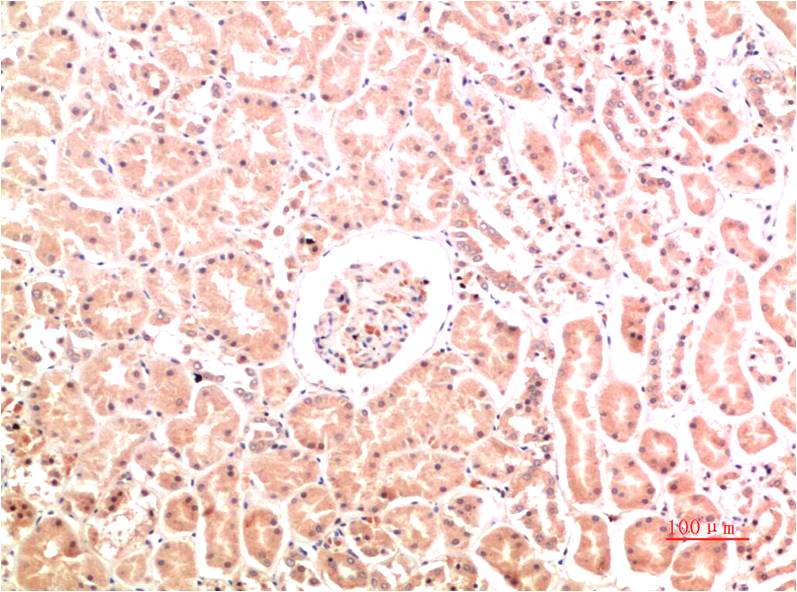

| Product Name: | Collagen IV Mouse Monoclonal Antibody(8E5) |

| Recommended dilutions: | IHC: 1:100-200 |

| Specificity: | The antibody can detects endogenous Collagen IV proteins. |

| Alternative Names: | BSVD, COL4A1, collagen type IV alpha 1 |